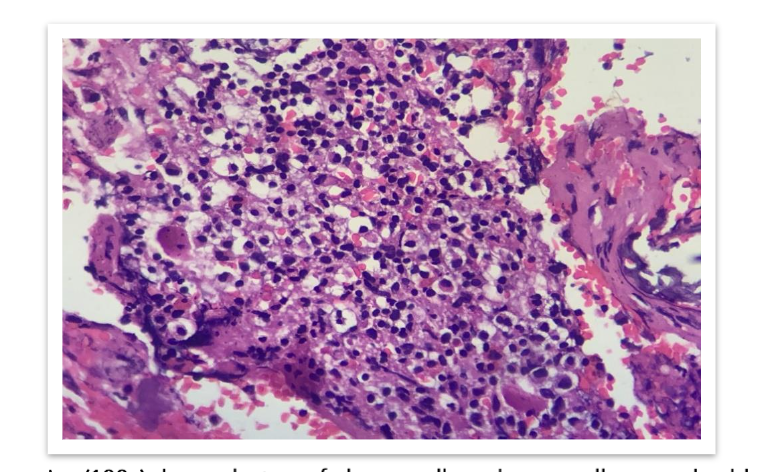

On gross examination, we received multiple grey brown to grey black soft tissue fragments altogether measuring 0.5cc, all the tissue was embedded in paraffin. Before grossing, tissue samples were fixed in 10% buffered neutral formalin. Sections were processed and stained with hematoxylin and eosin.

Microscopically, loosely arranged clusters of plasmacytoid cells, some are seen embedded in an eosinophilic osteoid like stroma. Few areas showed neutrophilic infiltration, spicules of degenerated bone, areas of haemorrhage and few bundles of striated muscle fibres. It was reported as Plasma cell malignancy- probably multiple myeloma (Non secretory type) as serum protein electrophoresis was normal.